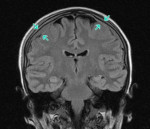

• Томографические исследования. Методы нейровизуализации имеют решающее значение в случаях скрытой нейролейкемии, при выявлении изменений цереброспинальной жидкости без соответствующей клиники заболевания. КТ головного мозга визуализирует очаги инфильтрации как гиподенсивные. Церебральная МРТ подтверждает наличие инфильтратов, позволяет более точно оценить их размер и расположение. Однако нейровизуализация не диагностирует природу инфильтратов, поэтому интерпретируется в комплексе с другими диагностическими данными.